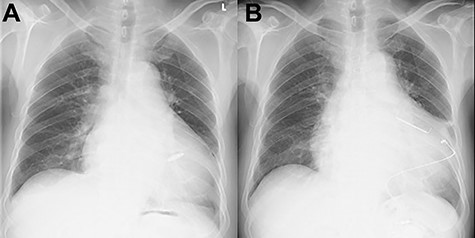

At his 1-year follow-up visit, the patient presented with shortness of breath on exertion and leg edema; thus, we decided to perform surgical correction. After median sternotomy, cardiopulmonary bypass was established with ascending aortic and bicaval venous cannulations. MyoPore (Greatbatch Medical, NY, USA) bipolar sutureless screw-in lead was attached to the left ventricle. A permanent PM was implanted, and left atrial appendage exclusion with AtriClip (AtriCure, OH, USA) was performed afterward. A right atriotomy was performed to facilitate exposure, wherein we found that the septal and posterior leaflets of the tricuspid valve were severely damaged (Fig. 3). Micra was placed over the right ventricular septum and was easily freed under direct vision (Fig. 4). After the leaflets were excised, an Epic (St Jude Medical, MN, USA) 33-mm bioprosthesis was implanted.

Intraoperative photograph; septal and posterior leaflet of tricuspid valve are severely damaged.